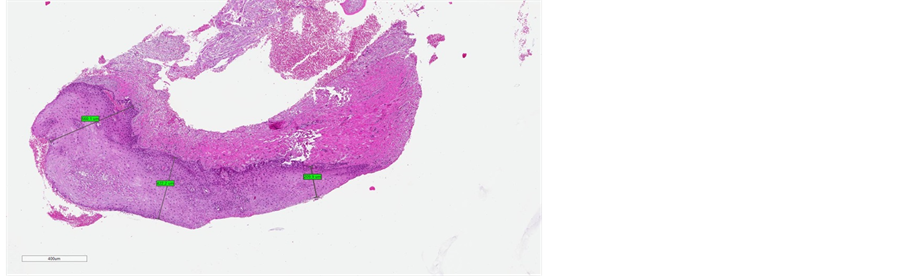

The laser therapy applied here induced neo-collagenogenesis, up regulated collagen type 3 expression, and increased epithelial papillae thickness, but due to limitations of the technique the degree of up regulation was not quantifiable. In addition. In addition, a significant enhancement of type III collagen production was observed in the lamina propria following treatment, likely to underlie its improved function, as well as the re-establishment of the physiological vaginal pH, probably due to the microbial lactobacillus flora (Figure 7 Figure 8). No side effects were observed and the procedure was well tolerated and did not require any local or systemic pharmacological or behavioural treatments. Of note, the ideal safety profile reported here can most likely be attributed to the stringent application of the study’s inclusion and exclusion criteria.

Figure 7. Post-treatment immunohistochemical evalu- ation of type III and IV collagen

Figure 8. (a)-(b) Evaluation of type III collagen using monoclonal antibody. (a) Vaginal mucosa before treatment. (b) vaginal mucosa after treatment: significant increase in the thickness and staining of the epithelium.